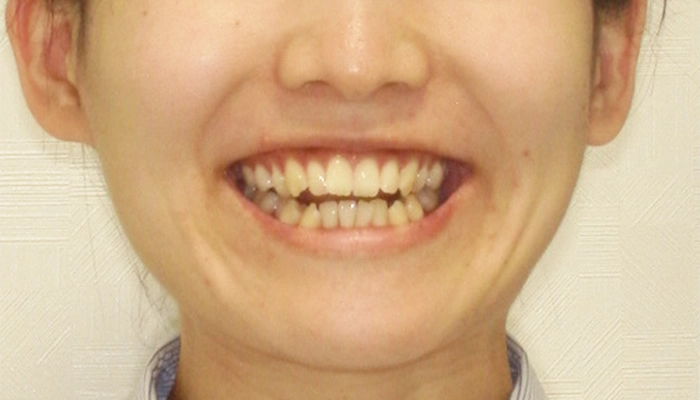

上下前歯のガタガタした歯並びが気になるとのことで当院に来院されました。

患者様のご希望は、矯正装置に希望は特にないが、なるべく治療期間を短くしたいとのことで、可能であれば部分矯正で治したいとおっしゃっていました。

精密検査や担当の矯正医の診断の結果、ワイヤー矯正よりマウスピース型矯正装置(インビザライン)の方が治療期間を短くできることが分かったため、そのことを患者様にお伝えしたところ、マウスピース矯正で治療することに決められました。

また、当初部分矯正を希望されていましたが、精密検査を行ったところ前歯だけではなく奥歯の噛み合わせの改善も必要でしたので、当院からはマウスピース型矯正装置(インビザライン)による全体矯正をご提案いたしました。